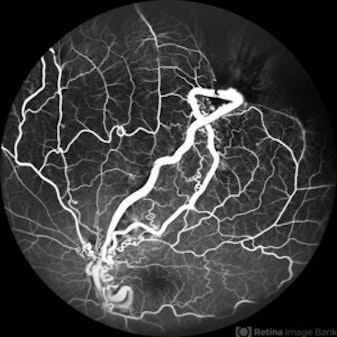

Wyburn-Mason Syndrome (Racemose Angioma)

Fundus photograph of a 10 year old child presenting with no perception of light in right eye. Fundus examination revealed dilated and tortuous retinal vessels suggestive of Racemose Hemangioma.

Category: Congenital abnormalities